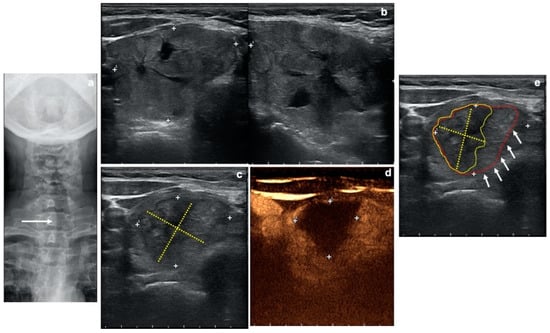

2.4. Radiofrequency-Ablated Volume Assessment